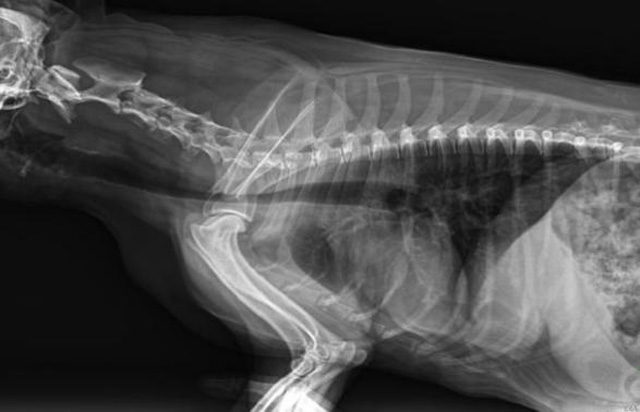

從臨床角度出發(fā),大力發(fā)展動(dòng)態(tài)DR,以精準(zhǔn)的診斷為小動(dòng)物保駕護(hù)航。寵物DR升級使用雙焦點(diǎn)球管,大尺寸平板探測器,超高頻逆變高壓發(fā)生器。醫(yī)用纖維板臺面,防止寵物劃傷。寵物DR整機(jī)小巧實(shí)用,骨略結(jié)構(gòu)和器官位置,分類詳細(xì),運(yùn)算更快,讓拍攝條件更科學(xué),有助于提高診斷的準(zhǔn)確性和效率。安裝移動(dòng)非常方便。低輸入電流設(shè)計(jì),220伏常規(guī)電壓。多品種動(dòng)物程序設(shè)定,滿足各個(gè)臨床需求。成像效果顯著,寵物不能言語表達(dá),導(dǎo)致誤診率居高不下。寵物診療均以經(jīng)驗(yàn)診斷為主的方式,確保最小化輻射降低對醫(yī)生及動(dòng)物的影響。以滿足精細(xì)化的寵物醫(yī)療需求,成為診斷寵物內(nèi)外科疾病的必備工具。使醫(yī)院更有競爭力,為醫(yī)院創(chuàng)收增光添彩。

寵物DR的操作流程是什么呢?第一步首先插上整機(jī)電源,然后按下主機(jī)電源。打開高壓發(fā)生器的電源,工作站主機(jī)電源。等待主機(jī)軟件的自動(dòng)啟動(dòng)。通過軟件登記檢查的寵物信息,選擇寵物檢查拍攝部位。調(diào)節(jié)限速器拍攝區(qū)域。關(guān)閉鉛房門,點(diǎn)擊開始拍攝按鈕。拍攝完成調(diào)整圖像并且輸出。